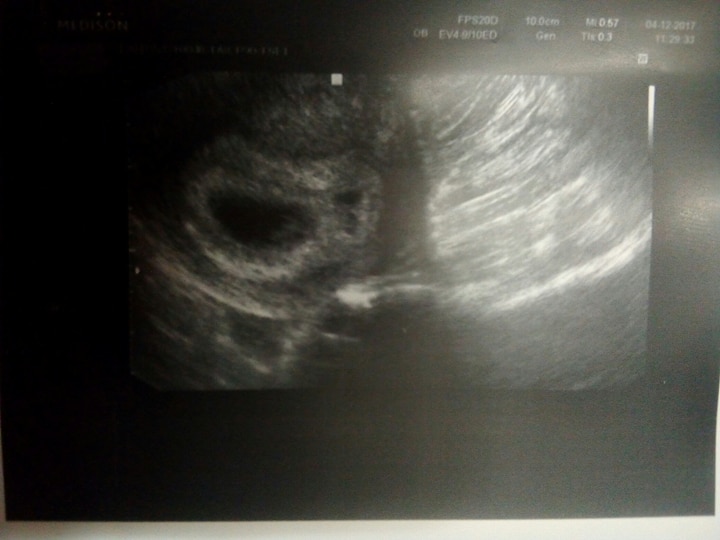

Čekáme miminko, resp.miminka 2. Na uz v 5+4tt byla vidět u A pouze dutinka a B doktor nevěnoval pozornost, ale maličká dutinečka tam byla vidět.

Další UZ jsem byla v 7+2tt a A byla dutinka s prospívajícím embryem odpov.týdnu a nad ním B, které dle dr zaniká.

Ale jak může zanikat, když za těch 12 dní tak vyrostlo? Četla jsem, že je i možné, aby dvojčata od sebe byla třeba delší čas, ale do hlavy my pořád nejde to, že zaniká, když vyrostlo.

Přidávám též obě fotky a moc děkuji za cokoliv, kdo mi napíše